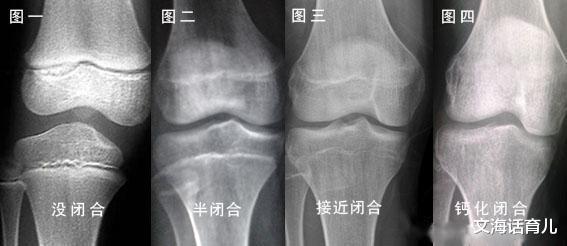

原来 , 增高药本身富含大量激素 , 药力使孩子性早熟 , 提前进入青春期 , 虽然骨龄跑得飞快 , 可是同时也加速了骨骺线闭合 , 让原本能持续长成的个头 , 提前终止了 。